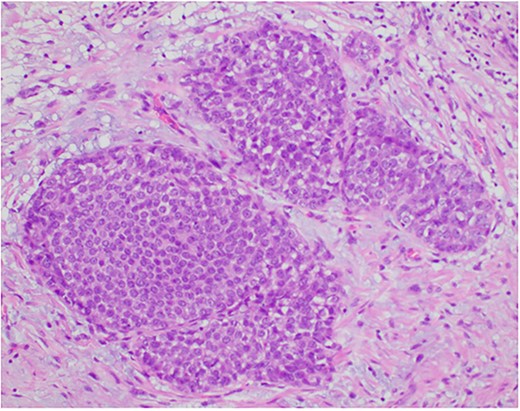

Photomicrograph showing a few ducts within the fibroadenoma expanded by a monotonous epithelial proliferation of classic lobular carcinoma in situ (arrows). (HE, ×20).

Photomicrograph showing the expanded ducts by classic lobular carcinoma in situ. (HE, ×200).